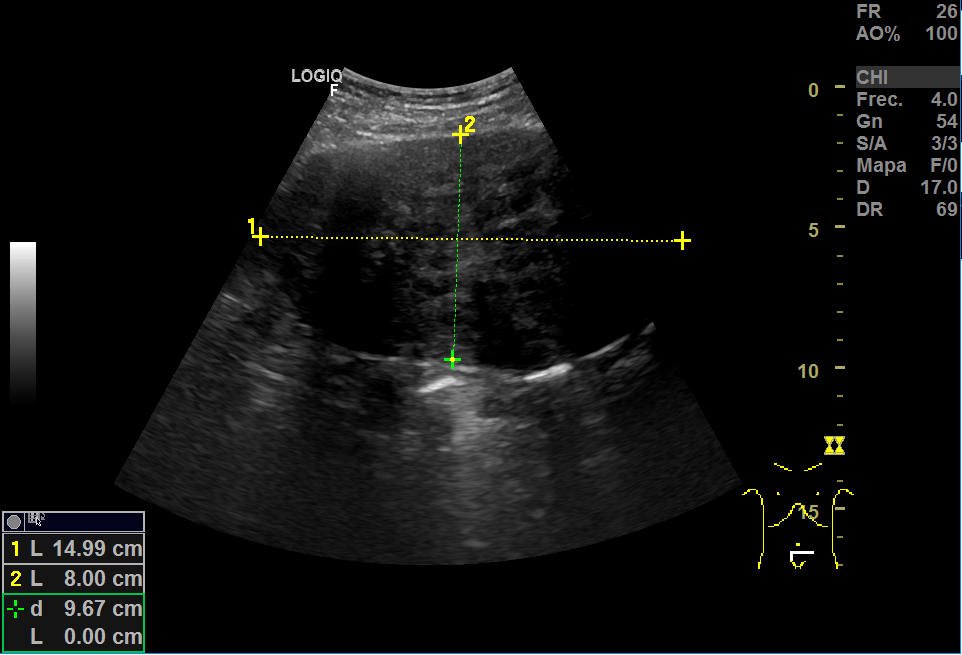

Realizamos una ecografía en el centro de salud y objetivamos, adyacente a útero, una imagen heterogénea de gran tamaño (15x8 cm), con vascularización, que podría corresponder a un mioma gigante. En anejo derecho, imagen redondeada de aproximadamente 3 cm en cuyo interior aparecen líneas hiperecogénicas en un fondo hipoecoico que podrían corresponder a teratoma, sin descartar otra patología. Ante la duda, derivamos a ginecología.

La RMN confirma la masa fibrótica de 11x8x10 en relación con mioma pediculado. Imágenes en la línea medida de fondo saco de Douglas de 55x46 y otra de 37x36, bien delimitadas, hiperintensas, compatibles con teratomas.